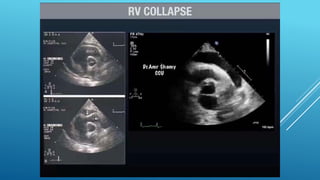

Phases of Hemodynamic changes in Tamponade,

Phases of Hemodynamicchanges in Tamponade, Phase I With Accumulation of pericardial fluid Impairs Relaxation and Filling of Ventricles, Requiring Higher Filling Pressure; during this phase, LV & RV Filling Pressures are Higher than IntraPericardial Pressure Phase II With further Fluid Accumulation, Pericardial Pressure increases Above Ventricular Filling Pressure, Resulting in Reduced Cardiac Output Phase III With further Decrease in Cardiac Output , which is due to Equilibration of :;: Pericardial and (LV) Filling pressures